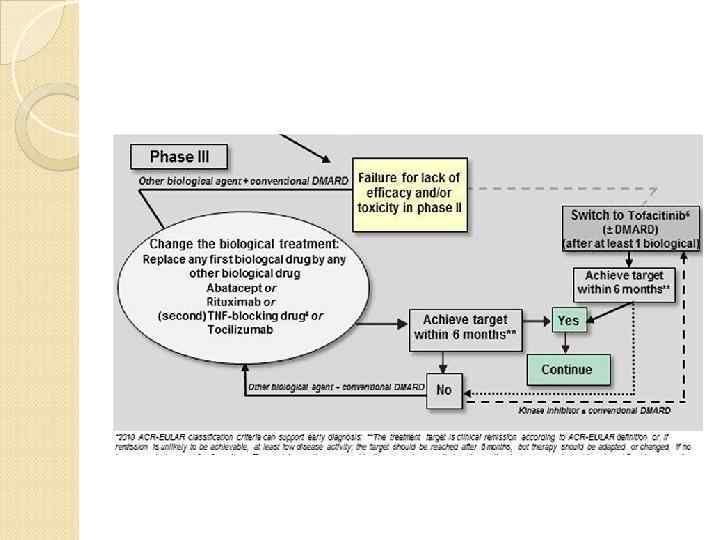

Фаза 3 Биологические агенты + синтетические БМ Недостаточный эффект или развитие побочных реакций на 2 фазе Изменить биологическую терапию: -второй ингибитор ФНО; или Ритуксимаб Тоцилизумаб абатацепт Достижение ремиссии или низкой активности через 3 -6 мес НЕТ ДА Продолжение

Фаза 3 Биологические агенты + синтетические БМ Недостаточный эффект или развитие побочных реакций на 2 фазе Изменить биологическую терапию: -второй ингибитор ФНО; или Ритуксимаб Тоцилизумаб абатацепт Достижение ремиссии или низкой активности через 3 -6 мес НЕТ ДА Продолжение